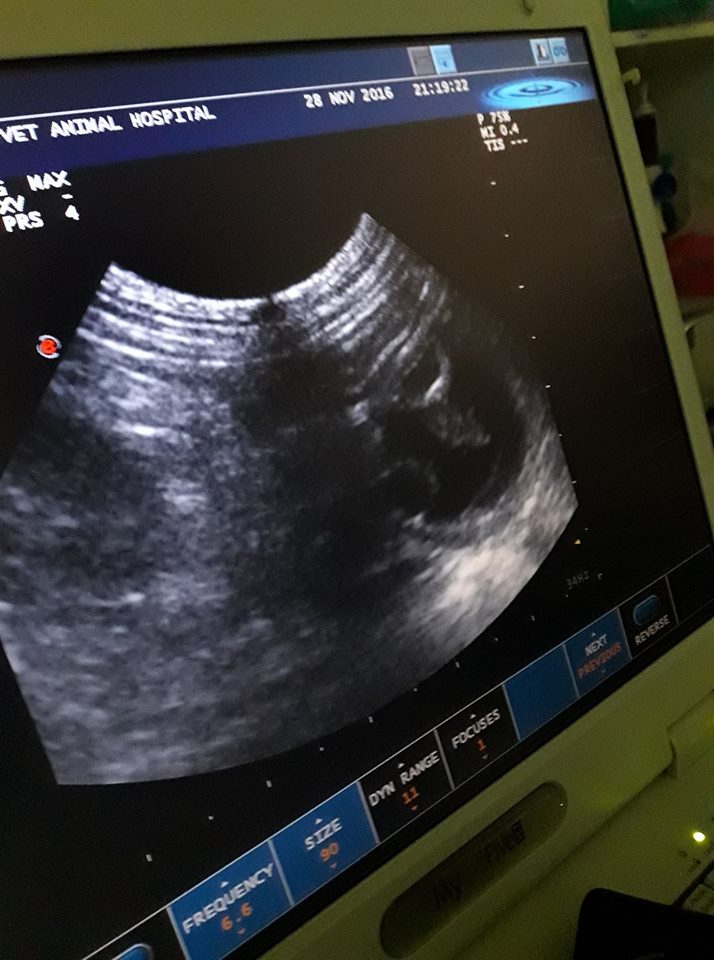

主題: 後腳拖行尾骨斷掉的懷孕母貓需要緊急醫療救援 申請者姓名: lois tsai 花色: 申請日期: 2016-12-21 00:38:35 申請者部落格: 申請者臉書網址: 所在縣市/合作醫院: 台北市/其他院所醫助專案(醫院請先MAIL溝通) 治療費用: 15800元 需求人數: 33人 已結案 (2022-05-13 15:20:47) 報名人員: Tina Tseng x2(已付款)、董珈瑄、Fox Yo(已付款)、lulumi x2(已付款)、Joe Shih(已付款)、王小盈(已付款)、Erin Lin x2(已付款)、Freesia Tsai(已付款)、PIN(已付款)、Mia Jheng(已付款)、SweetTpg(已付款)、Ashley(已付款)、ChrisLin x4(已付款)、Wenny Chen(已付款)、Isa喵(已付款)、惠青(已付款)、劉熊妹(已付款)、徐雅嬪(已付款)、小蘋塔羅的客人們(已付款)、Rainpi(已付款)、yuju x2(已付款)、Aisha Lung(已付款)、李嘉芸(已付款)、HTLE(已付款)、攸yu x3(已付款)、 候補人員: 動物病情說明: 11/28 早上志工接到通報市場內有傷貓後肢拖行,誘捕後帶到附近動物醫院。晚上轉診,X光確診尾巴斷了,超音波確定有懷孕2~3周大小貓胎兒,膀胱積尿,有血尿, 薦椎裂開。然而不確定薦椎旁的後腳神經是否受損, 貓咪有沒辦法自己排尿排便, 小貓不確定是否能存活。所以就先帶回來觀察了,但隔天貓咪狀況不佳,狀況不佳,不吃不喝不動,昨晚又帶去醫院血檢,貧血加上血尿,醫生建議輸血,我也緊急找到了血貓明天去配對,希望能給牠爭取一些時間看看能不能有機會治療復原。 動物近況說明: 早安已能自己排尿排便